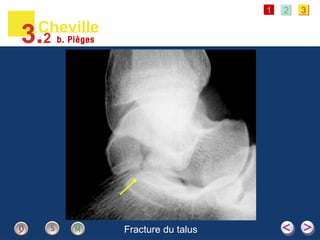

Fracture du talus

• #29 Radiographie de profil focalisée sur le talus d’un jeune patient qui présentait une douleur après une chute. Ce cliché révèle une fracture de la face postéro-inférieure du talus avec un trait de refend articulaire à l’articulation sous-talienne postérieure [flèche jaune]. Ce type de fracture est assez inhabituel et peut donc être facilement ignoré par une lecture trop rapide des clichés. Apparition du titre